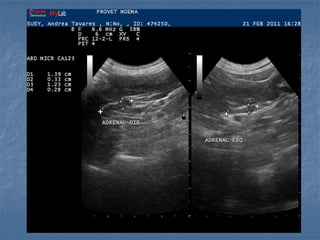

Hiperplasia adrenal bilateral

 Hiperadrenocorticismo  Hipofisáriodependente: há um aumento bilateral (80% dos casos!), pode ser simétrico ou assimétrico * Medida normal de espessura menor que 0,74cm cães adultos